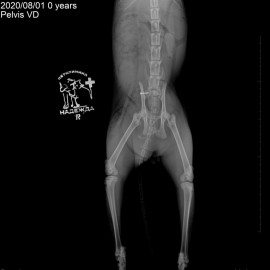

Котик Персик после покуса собаки. Обратились с жалобами на отсутствие опороспособности на левую переднюю и задние лапы. После рентгенографического исследования поставлен диагноз: вывих левого локтевого сустава, перелом костей правого крестцово-подвздошного сочленения, перелом лонной и седалищной костей таза. Проведена операция: остеосинтез левого локтевого сустава, остеосинтез правого крестцово-подвздошного сочленения таза.

Снимки 1-2 до операции